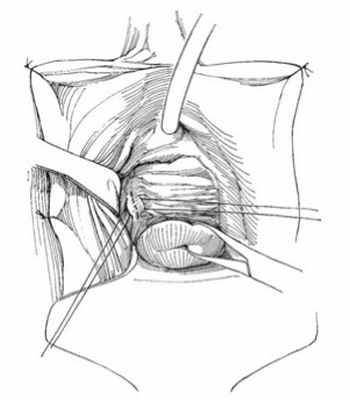

28.10.2019 выполнен второй этап — реконструктивно-восстановительный — в объеме тонкокишечной пластики влагалища (рис. 2 и 3, на цв.вклейке) сформированы ортотопический тонкокишечный мочевой пузырь, неоуретра.

Рис. 2. Интраоперационная фотография после выполненного адгезиолизиса, визуализирована полость малого таза, задняя стенка влагалища (указана стрелкой).

Рис. 3. Передняя стенка влагалища (указана стрелкой), сформированная из сегмента тонкой кишки (интраоперационная фотография).